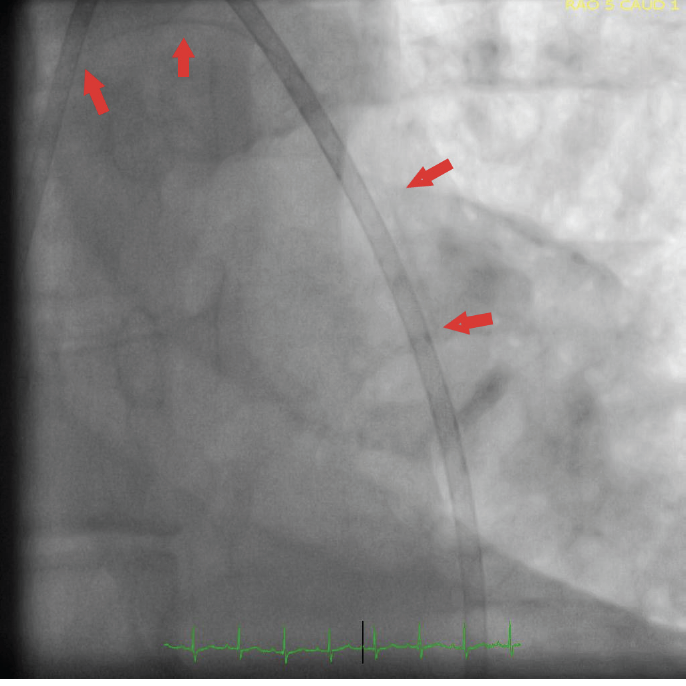

A 75-year-old man was referred to our clinic from another center following his complicated percutaneous coronary intervention (PCI) performed in the setting of an acute coronary syndrome. Angiographic images obtained during PCI demonstrated sequential implantation of 2 drug-eluting stents at the mid (3.0 x 28 mm) and proximal (4.5 x 19 mm) portions of the right coronary artery. However, the images also demonstrated a high-degree underexpansion of the proximal larger stent along with its jailed balloon. It was also reported by the performing interventionalist that he had attempted to pull back the balloon of the implanted proximal stent swiftly (before it was completely deflated) just following unplanned disengagement of the guiding catheter from the right coronary ostium. However, this maneuver resulted in abrupt balloon shaft fracture (outside the guiding catheter) leading to a freely swinging shaft appearance in the descending aorta (Figure 1 and Figure 2). Unfortunately, several attempts to retrieve the swinging fragment of the shaft failed. Moreover, intracoronary snare technique in an effort to grasp the distal portion of the shaft also failed. Finally, the shaft fragment was surgically removed (Figure 3) along with a bypass graft operation for the severely stenotic circumflex artery.